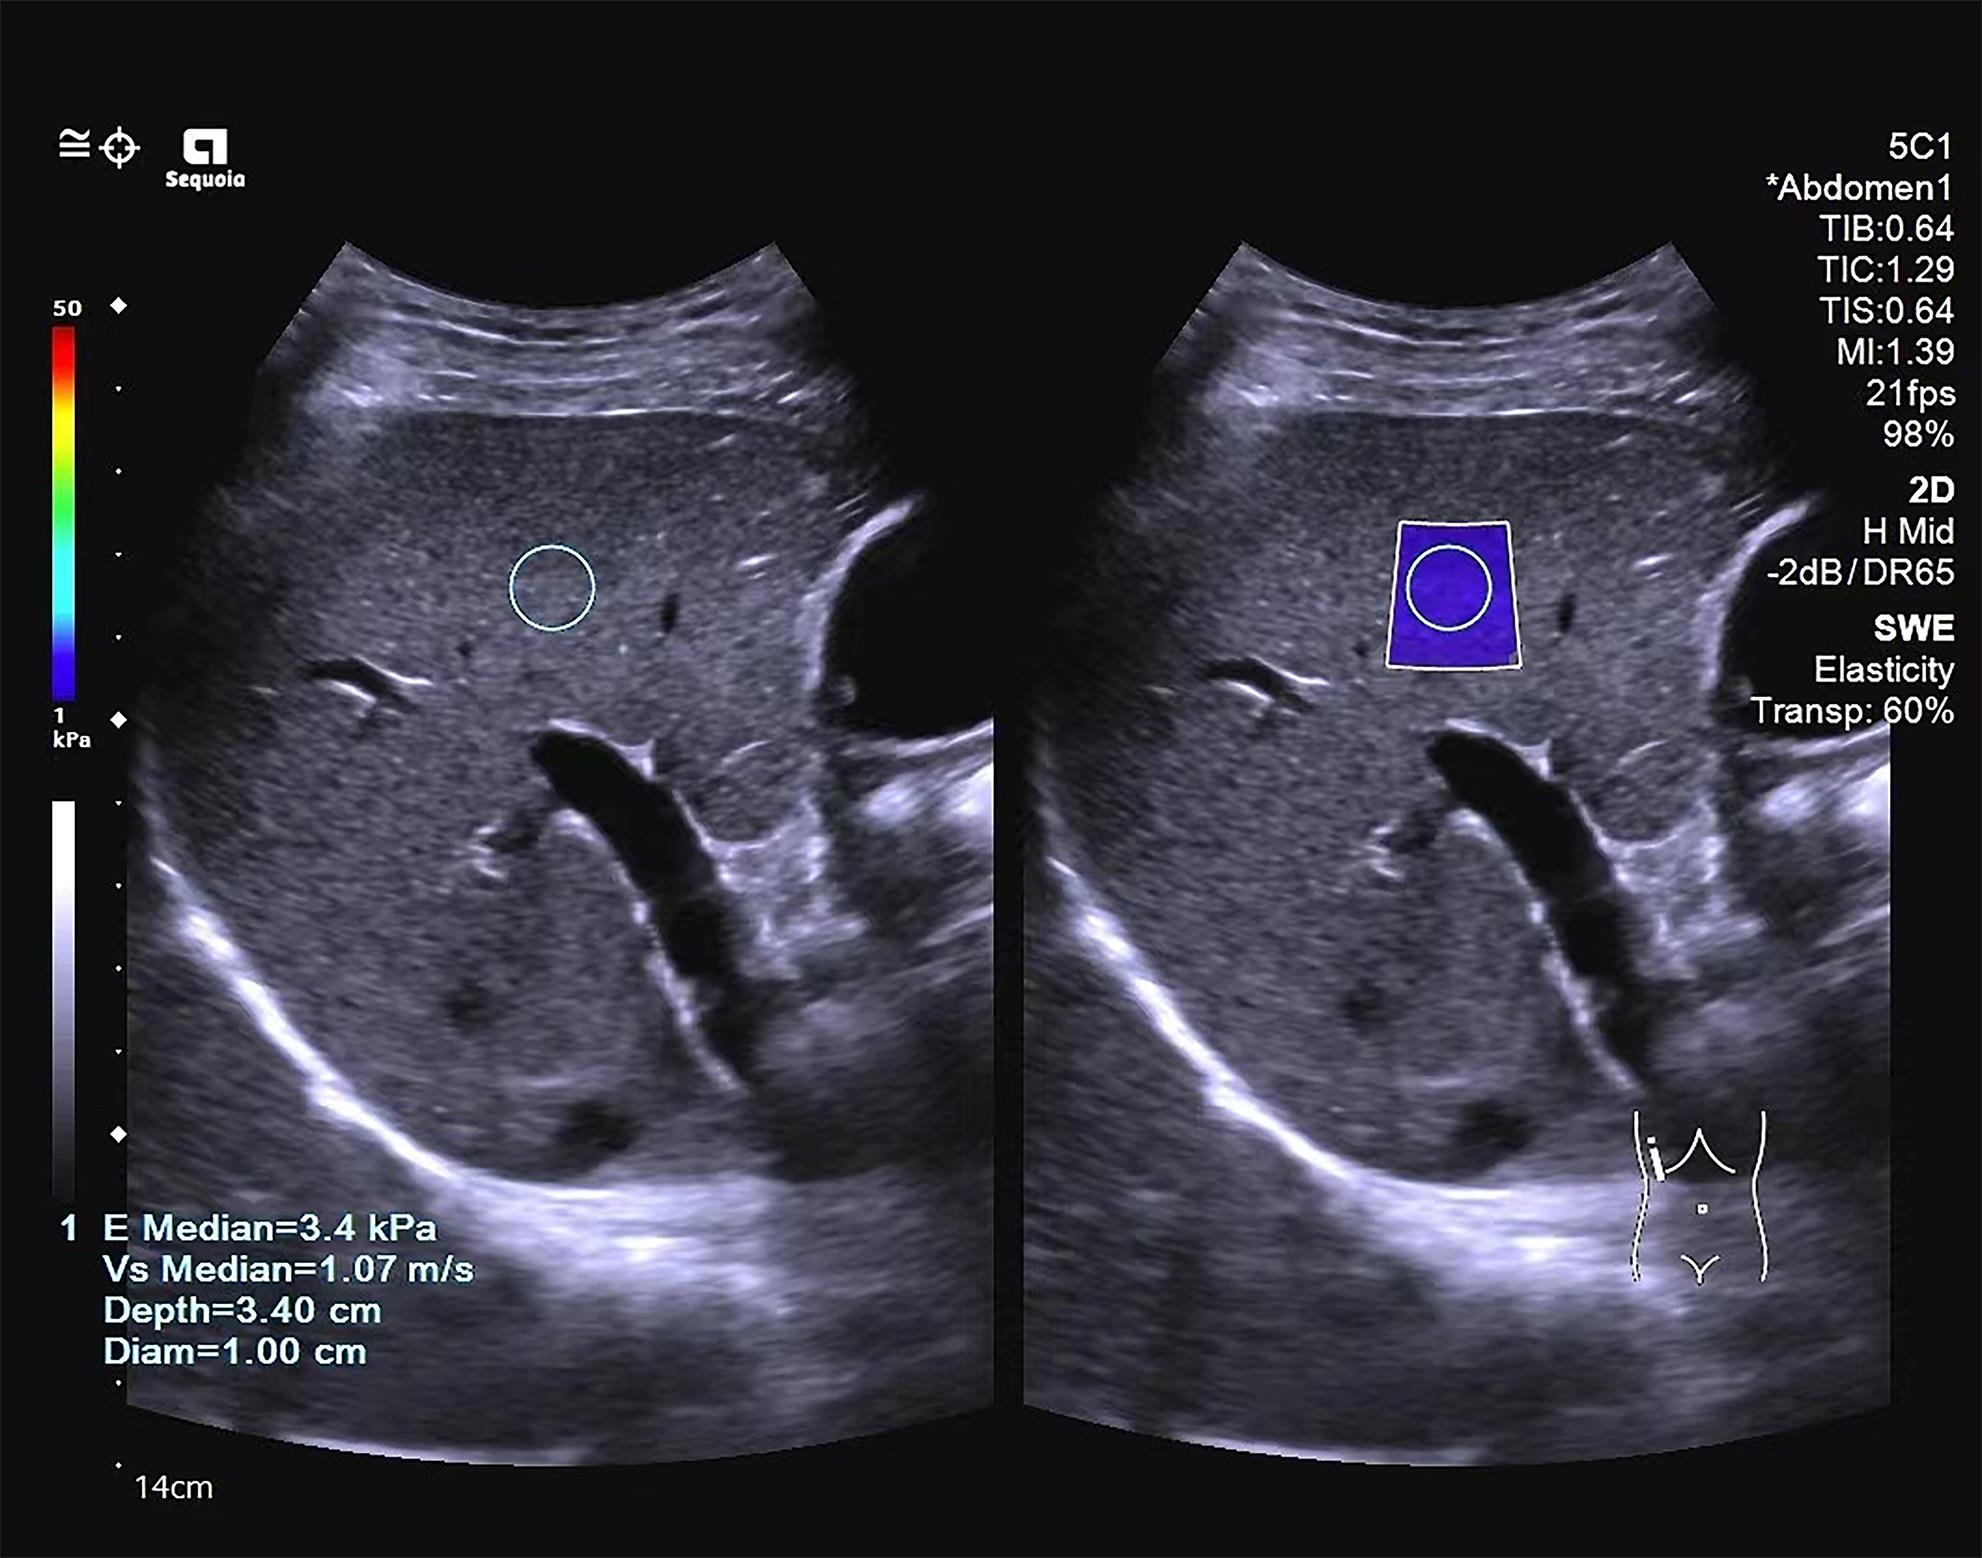

Application value of two-dimensional shear wave elastography and serological models in the staging of liver fibrosis in patients with chronic hepatitis B

Yujie HUANG, Siyi FENG

2024, 40(3): 509-515. DOI: 10.12449/JCH240312

Abstract(1105) HTML (276) PDF (1188KB)(83)

Abstract:

Objective  To investigate the value of two-dimensional shear wave elastography (2D-SWE) or serological models used alone or in combination in determining the stage of liver fibrosis in patients with chronic hepatitis B.  Methods  A retrospective analysis was performed for the clinical data of 327 patients with chronic hepatitis B who were admitted to Mengchao Hepatobiliary Hospital of Fujian Medical University from August 2020 to August 2022 and underwent 2D-SWE and liver histopathological examination, including sex, age, serological markers, and 2D-SWE results. According to the degree of liver fibrosis, they were divided into S0-S1, S≥2, S≥3, and S=4 groups, and the serological models were calculated based on serological markers. A Spearman correlation analysis was used to investigate the correlation of 2D-SWE and serological models with liver fibrosis stage; the receiver operating characteristic curve was plotted with the results of liver histopathology as the standard to compare the efficiency of each parameter used alone or in combination in determining the stage of liver fibrosis; the Delong test was used to investigate the difference between different methods.  Results  Liver stiffness measurement measured by 2D-SWE was strongly correlated with the stage of liver fibrosis (r=0.741, P<0.001), and as for the serological model, six markers (APRI, FIB-4, GPR, GP, RPR, and S index), other than AAR, were positively correlated with the stage of liver fibrosis (all P<0.001). 2D-SWE had an area under the ROC curve (AUC) of 0.878, 0.932, and 0.942, respectively, in the diagnosis of S≥2, S≥3, and S=4 liver fibrosis (all P<0.001), with an optimal cut-off value of 6.9 kPa, 7.9 kPa, and 9.4 kPa, respectively. Among the serological models, APRI had the largest AUC of 0.788 and 0.875, respectively, in the diagnosis of S≥2 and S=4 liver fibrosis, and S index had the largest AUC of 0.846 in the diagnosis of S≥3 liver fibrosis. In the diagnosis of S≥2, S≥3, and S=4 liver fibrosis, 2D-SWE combined with APRI increased the AUC values to 0.887, 0.938, and 0.950, respectively, and 2D-SWE combined with S index increased the AUC values to 0.879, 0.935, and 0.941, respectively, while there were no significant differences between 2D-SWE and the above combinations (P>0.05).  Conclusion  2D-SWE has a better diagnostic efficacy than the above seven serological models in determining liver fibrosis stage. The serological models have a certain diagnostic value, among which APRI and S index have a relatively high diagnostic value. There is no significant difference between 2D-SWE and 2D-SWE combined with serological models, and such combinations cannot significantly improve diagnostic efficiency. Therefore, further studies are needed to explore new combinations of diagnostic methods.